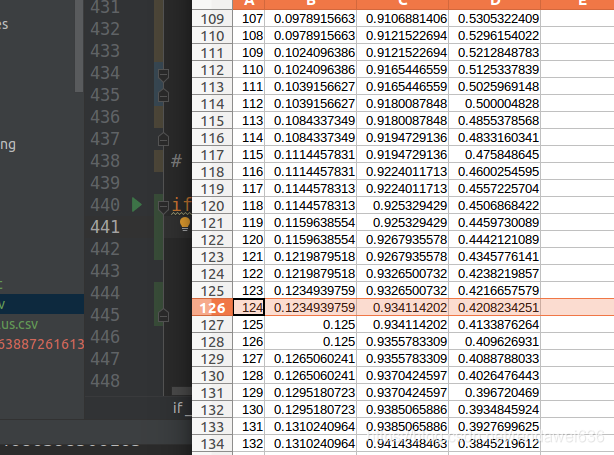

三、训练结果

我们从数据库中,标记了大概11000个肺结核,11000个负样本。ROI图如下